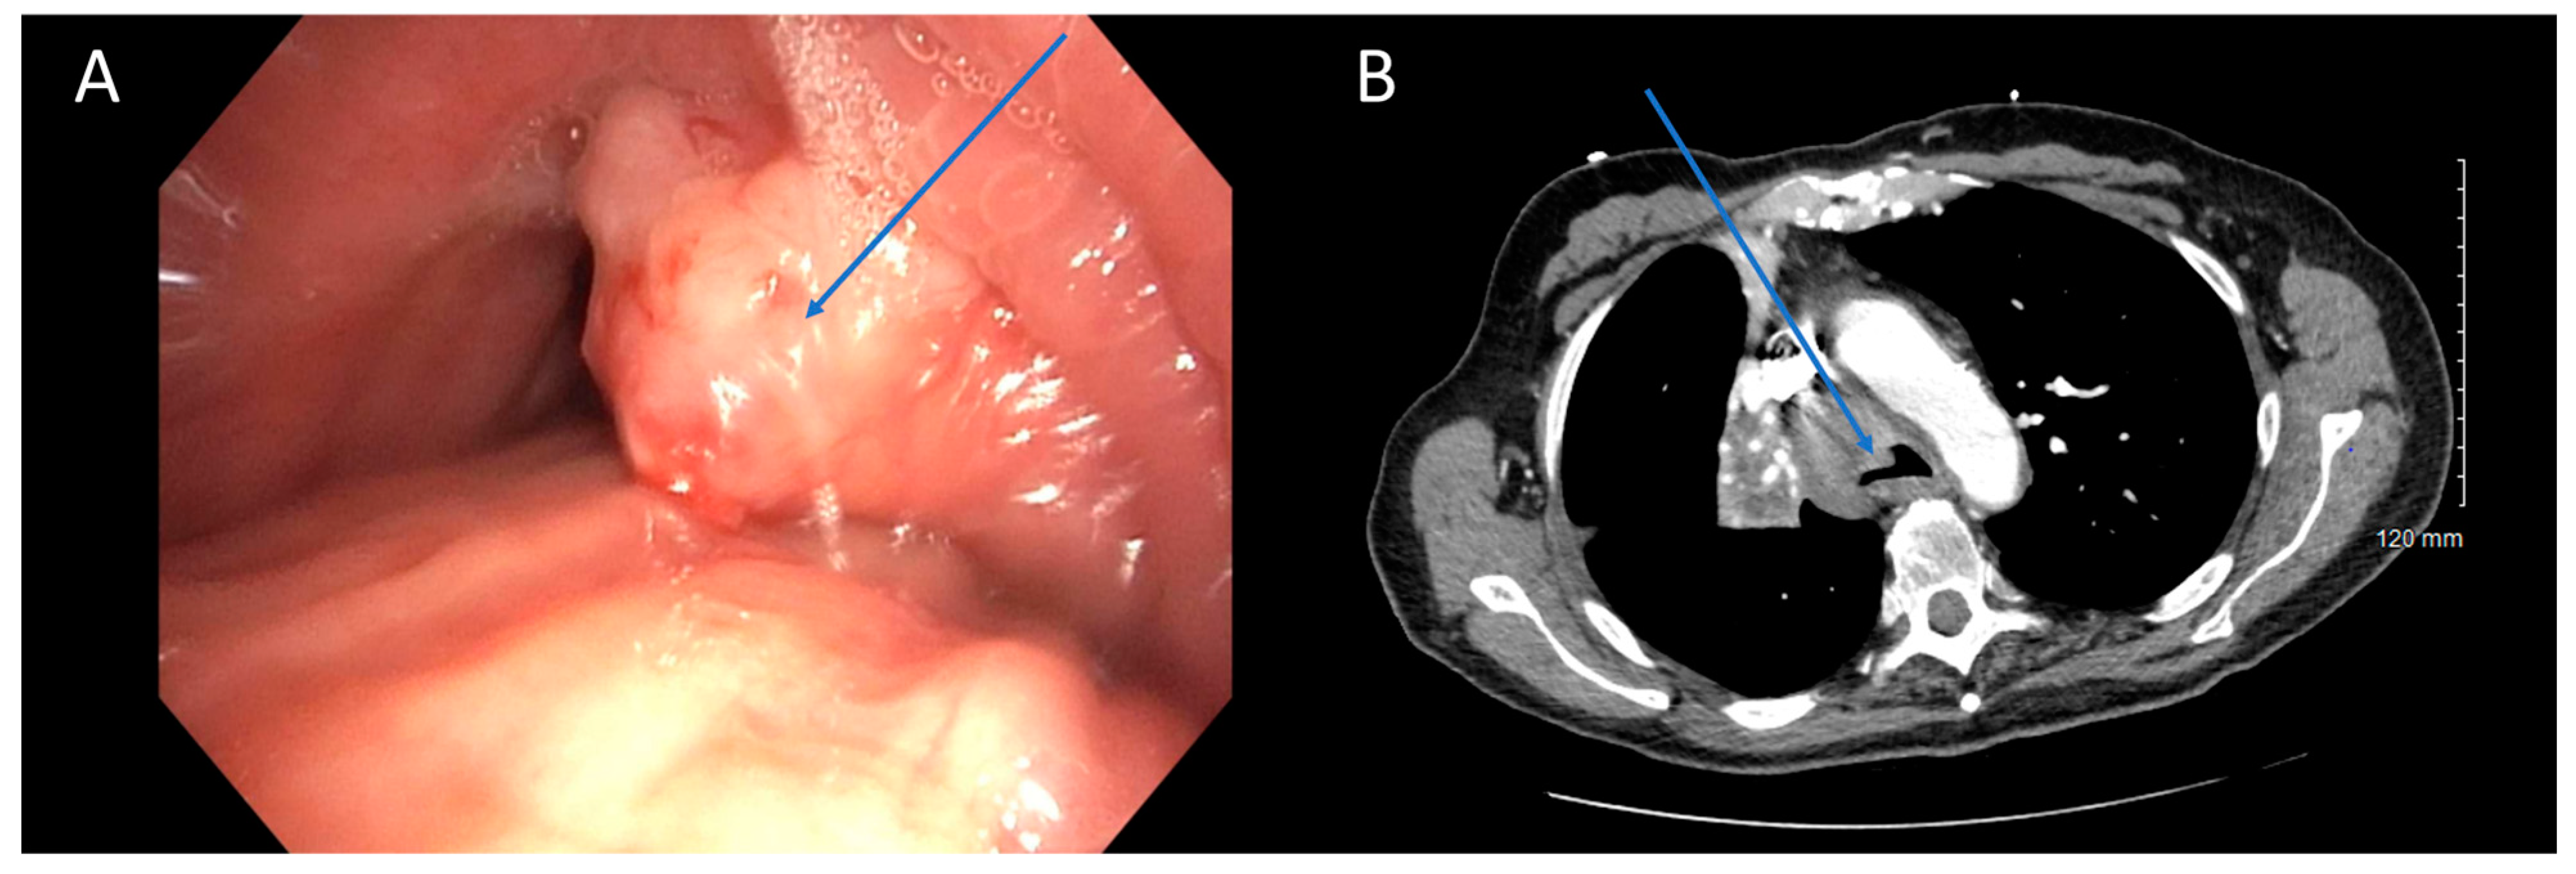

Figure 1.

CT Underestimating Degree of Obstruction Compared to Bronchoscopy. Bronchoscopy (A) and CT (B) images depicting an endobronchial tumor in the distal trachea of a patient. The severity of obstruction appears to be greater when observed bronchoscopically compared to CT imaging. Arrows (in blue) highlight the tumors in the figure.

Our analysis revealed moderate to good agreement between bronchoscopy and CT regarding the subtype of obstruction (81% agreement, Cohen’s κ = 0.683, p < 0.001). There was excellent concordance between the two modalities when subtype was identified as extrinsic (15/17, 88%) or intrinsic (24/27, 89%) on bronchoscopy. The primary area of disagreement was that a number of cases were characterized as extrinsic disease on CT (13/60, 22%) when they were mixed on bronchoscopy. One possible explanation is that bronchoscopy may unveil features not easily discernible on CT scans. It is possible that extrinsic and mixed obstruction exist on a spectrum, with luminal wall edema and luminal wall tumor infiltration existing in obstruction that is more heavily extrinsic, but still with some mixed component [26]. Bronchoscopy’s ability to detect these nuances enables a classification of mixed subtype, which may not be as evident on standard 5 mm CT scans (Figure 2). Higher resolution CT scans with virtual bronchoscopy reconstruction might enhance the identification of such subtleties [27]. In a previous study by Naidich et al., CT scans were found to accurately identify focal airway lesions with 90% accuracy. However, the study concluded that axial CT scans were inaccurate in predicting whether the abnormality would be endobronchial, submucosal, or extrinsic [28]. Finkelstein et al. conducted a study involving 44 patients using super high-resolution CT scanning, revealing sensitivities for the detection of endoluminal, obstructive, and mucosal lesions at 90%, 100%, and 16%, respectively [29]. Another retrospective study by Mamatha et al., involving 426 patients, found the sensitivity of CT in detecting abnormal mucosa, endobronchial masses, and extrinsic compression to be 27.50%, 89.00%, and 59.52%, respectively [30]. Although these studies primarily focused on identifying focal airway abnormalities in both healthy and diseased patients, rather than specifically characterizing central airway obstruction, a consistent trend emerges indicating poor characterization of mucosal lesions. This aligns with our observations that mixed diseases with predominantly extrinsic component might be erroneously interpreted solely as extrinsic on CT due to its inability to detect mucosal abnormalities. Mixed disease should be less prone to being misinterpreted as intrinsic disease, since intrinsic airway compression should be recognizable on both imaging and bronchoscopy, consistent with our findings. Based on the above findings, we recommend exercising caution when extrinsic disease is identified on CT scans, as there is a risk of overlooking potential intrinsic disease components. We advocate for maintaining flexibility in treatment approaches, particularly by considering bronchoscopy for further evaluation when extrinsic disease is suspected based on CT findings.

CT is Poor at Identifying Mucosal Component of Malignant Central Airway Obstruction. Bronchoscopic (A) and CT (B) images illustrating malignant central airway obstruction in the right main stem bronchus of the same patient. The CT image suggests primarily extrinsic obstruction, whereas bronchoscopy reveals a combination of extrinsic and intrinsic disease (mixed subtype). Arrows in blue indicate the tumors, while the black circle in (A) highlights the mucosal edema visible during bronchoscopy.